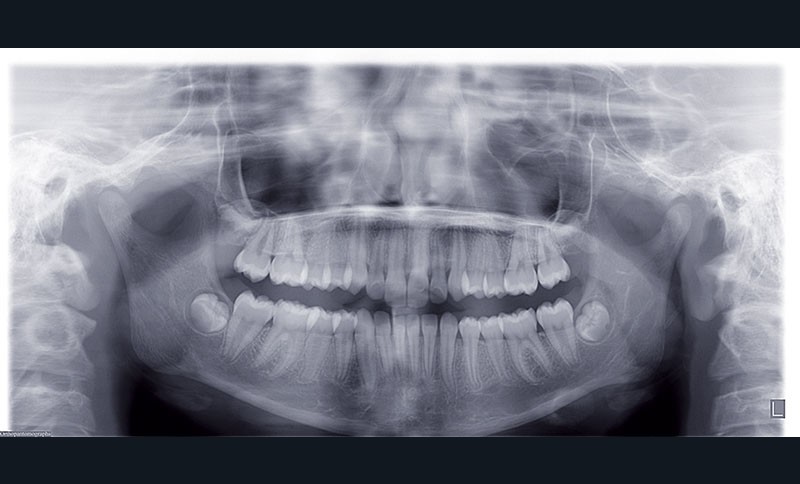

Nous sommes en présence d’une patiente adolescente âgée de 12 ans ½ dans une phase de croissance faciale favorable.

Elle présente une classe II squelettique par rétrognathie mandibulaire et une classe II dentaire molaire et canine droite et gauche associée à une biproalvéolie incisive maxillaire et mandibulaire.

L’environnement vertical est normodivergent.

Le pronostic de correction de la classe II est favorable mais il est très important de souligner la vestibuloversion incisive mandibulaire et le risque parodontal associé (fig. 1 à 3).